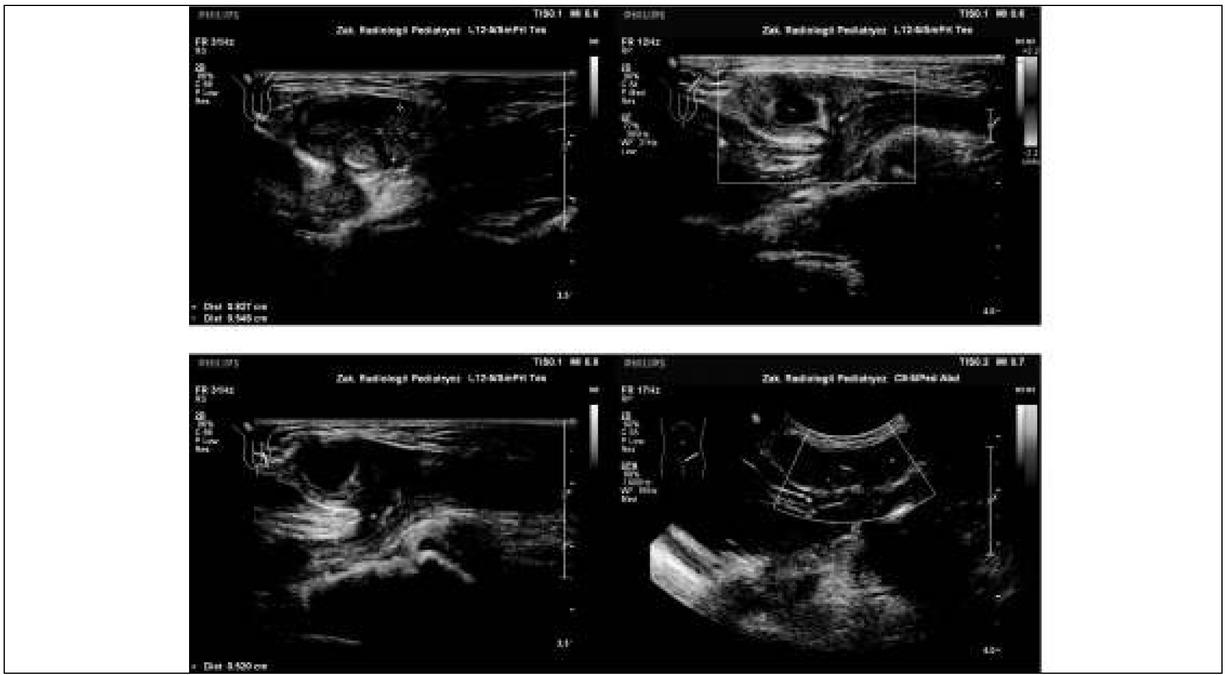

Fig. 1

Fig. 2

Fig. 3

| 1 | 3 | left lewa | prematurity wcześniactwo | incarcerated intestinal loop with grossly diminished blood flow uwięźnięta pętla jelitowa ze znacznie zmniejszonym przepływem slightly enlarged ipsilateral testis, abnormal testicular structure with visible blood flow nieznacznie powiększone jądro, nieprawidłowa struktura jądra, widoczny przepływ krwi przez jądro | 12 hrs 12 godz. |

| 2 | 4 | right prawa | incarcerated intestinal loop with diminished blood flow uwięźnięta pętla jelitowa ze zmniejszonym przepływem enlarged ipsilateral testis, normal testicular structure, blood flow not estimated powiększone jądro, prawidłowa struktura jądra, bez oceny przepływu krwi | 5 hrs 5 godz. | |

| 3 | 5 | right prawa | incarcerated intestinal loop with visible blood flow uwięźnięta pętla jelitowa z widocznym przepływem enlarged ipsilateral testis, slightly abnormal testicular structure, blood flow not estimated powiększone jądro, nieco nieprawidłowa struktura jądra, bez oceny przepływu krwi | 6 hrs 6 godz. | |

| 4 | 10 | left lewa | prematurity wcześniactwo | incarcerated intestinal loop with visible blood flow uwięźnięta pętla jelitowa z widocznym przepływem normal ipsilateral testis, blood flow not estimated prawidłowe jądro, bez oceny przepływu krwi | 4 hrs 4 godz. |